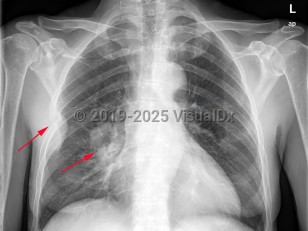

Lung cancer

Greater than 95% of lung cancers can be categorized as either small cell lung cancer (SCLC) or non-small cell lung cancer (NSCLC), with adenocarcinoma and squamous cell carcinoma being the most common NSCLC. Carcinoid tumors and mesothelioma may also arise in the lung but are less common. The lungs are also a common site of metastatic cancer.

Some tumors may be associated with multiple metastases to the lung, which can cause rapid onset of pulmonary hypertension. Sometimes, cancer may invade the esophagus and cause a bronchoesophageal fistula. Lung cancer is a common cause of obstruction of the superior vena cava and superior vena cava syndrome. Cushing syndrome is a common paraneoplastic association.